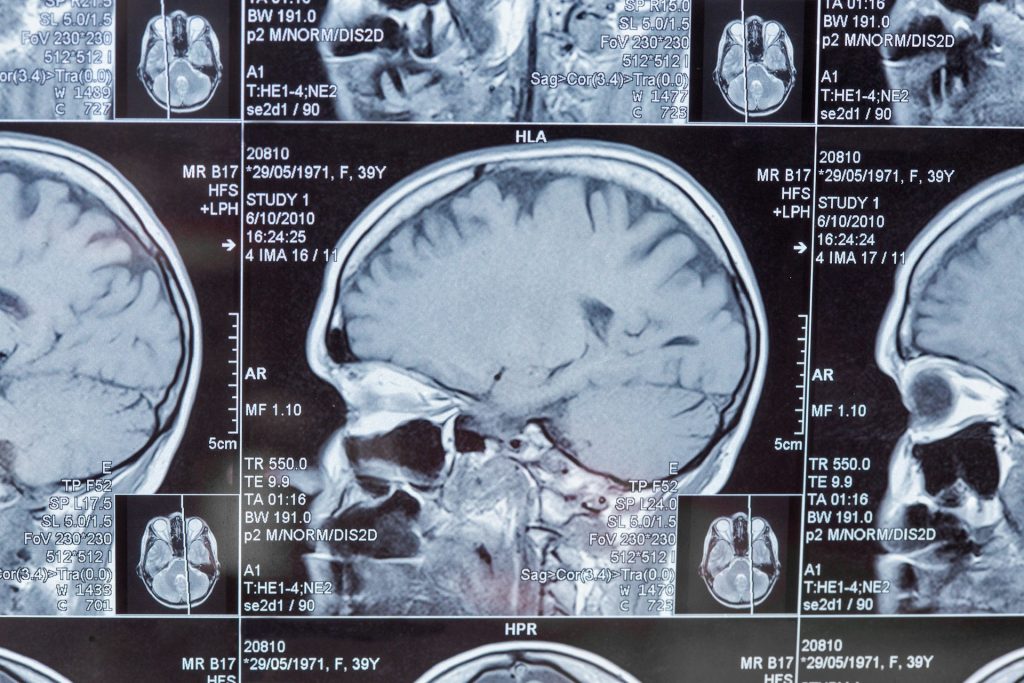

New Light Probe for Early Detection of Brain Metastases

New ultra-thin light probe enables non-invasive monitoring of brain changes, offering potential for early detection of metastases and neurological disorders.